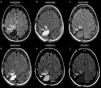

ResultsA total of 107 patients were included, of whom 90 had high-grade gliomas. Inter-rater agreement was excellent, and intra-rater complete (k=0.94 and 1, p<.001). Hyperintense fluid in the resection cavity occurred more commonly (58.9% versus 29.4%, p=.025) and earlier (mean 4.5 versus 9.9 months, p<.001) in high-grade than in low-grade gliomas. Hyperintense fluid was associated with progression in high-grade gliomas, with a sensitivity of 65.7% (95%CI, 54.3–75.6%) and a specificity of 70.6% (95%CI, 46.6–87%), and in low-grade gliomas with a sensitivity of 50% (95%CI, 18.7–81.2%), and a specificity of 81.8% (95%CI, 51.1–96%). The positive predictive value of this sign was 90.6% (95%CI, 79.3–96.3%) for high-grade gliomas, and was higher for grade IV (93.2%, 95%CI, 87.3–99.1%) and lower for grade III (77.8%, 95%CI, 59.6–96%), and low-grade gliomas (60%, 95%CI, 22.9–88.4%). False-positives were identified in 7 patients, due to bleeding or infection. Hyperintense fluid in high-grade gliomas preceded progression in 22 patients (30.1%), with a mean of 4.1 months (SD 2.1, 95% CI, 3.2–5), and associated with poorer progression-free survival (mean 6.8 versus 11.7 months, p=.004).

ConclusionsHyperintense fluid in the resection cavity on follow-up FLAIR sequences occurs more frequently and earlier in high-grade gliomas, and is associated with poorer progression-free survival. Hyperintense fluid is associated with disease progression, and can predict the progression of resected gliomas. False-positives due to bleeding and infection can be observed, and are easily recognizable.